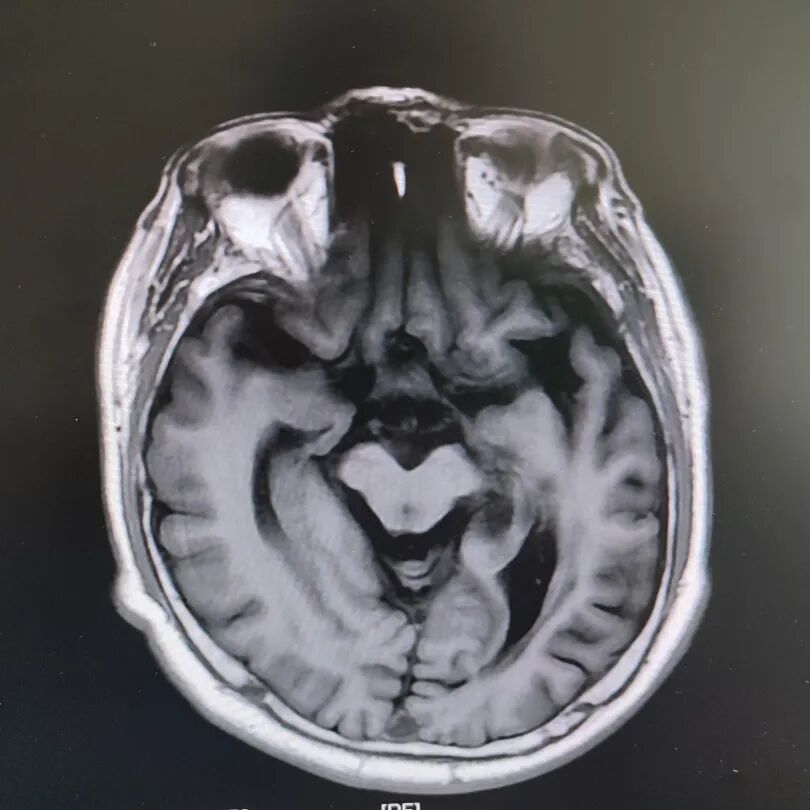

患者頭部磁共振影像

就在看似陷入僵局時,關鍵的血液檢查結果出來了——RPR陽性!這個結果像一盞明燈,指明了方向。原來,導致大爺眼病的幕后黑手,竟是由蒼白密螺旋體(引起梅毒的病原體)感染引起的神經損害。經過針對性治療,十幾天后,大爺的病情逐漸好轉,眼皮能抬起來了,重影消失了,眼球轉動也靈活了!